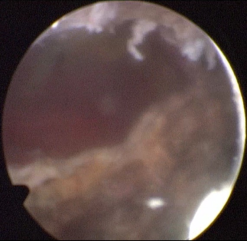

巨大的前列腺肿瘤占据整个盆腔,明显挤压尿道及直肠

剜除术后巨大的前列腺窝